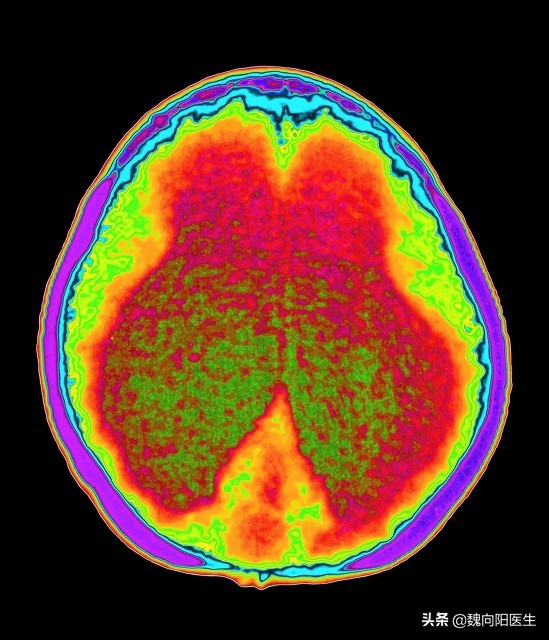

第三种就是由于#脑积水#所引起的痴呆。这一类人是由于脑外伤、蛛网膜下腔出血或其他的因素所导致的颅内脑脊液分泌增多、脑脊液循环不畅或脑脊液回吸收障碍,最终导致脑室扩大压迫正常脑组织而引起的认知功能障碍。

对脑积水引起的痴呆,通过脑室腹腔分流术可以明显的减少颅内的脑积液对正常脑组织的压迫,使认知功能得到极大的恢复。

脑积水性痴呆是可以通过手术的办法彻底解决的。